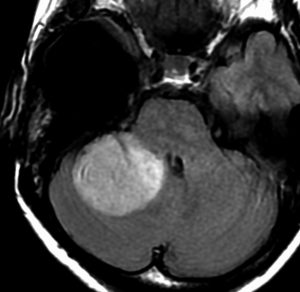

その2年後の画像です。右小脳半球に再発しています。右側頭葉腫瘍との連続性は全くありませんでした。脳幹部にも腫瘍はありません。遠隔再発 remote recurrenceというもので,星細胞系腫瘍 astroytic tumor AAやGBMではよく知られている現象です。乏突起膠細胞系腫瘍でもまれにみられます。